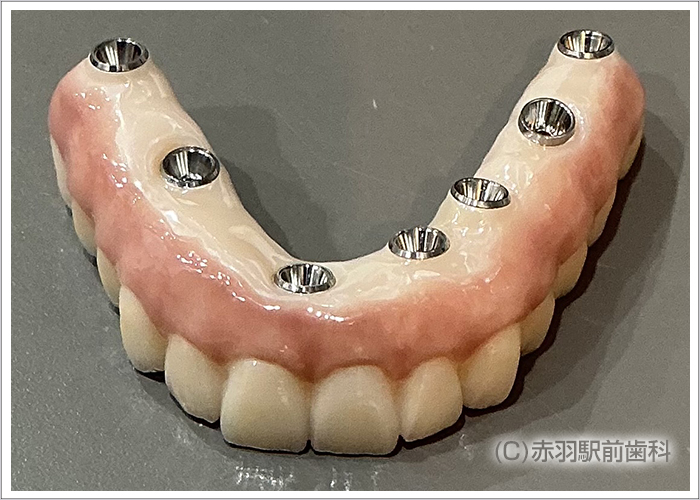

↑下顎の歯はハードレジン製の連結した人工歯です。経年劣化によって汚れがついてきたり摩耗するデメリットがあります。 ![]()

CTデータから事前に3Dプリンターで、患者様の実寸代の顎骨模型を作成しておいて手術前にシミュレーションで担当医がインプラント埋入とSRAアバットを装着しておきました。画像は下顎の模型です。両サイドのインプラントはオールオン4特有の傾斜埋入をしてあります。

上下に最終的な上部構造の人工歯をスクリュー固定した状態です。内部の見えない部分をチタンフレームで補強して歯肉をハイブリットセラミックで加工。人工歯はジルコニアの歯を1本ずつ仕上げて完成しました。